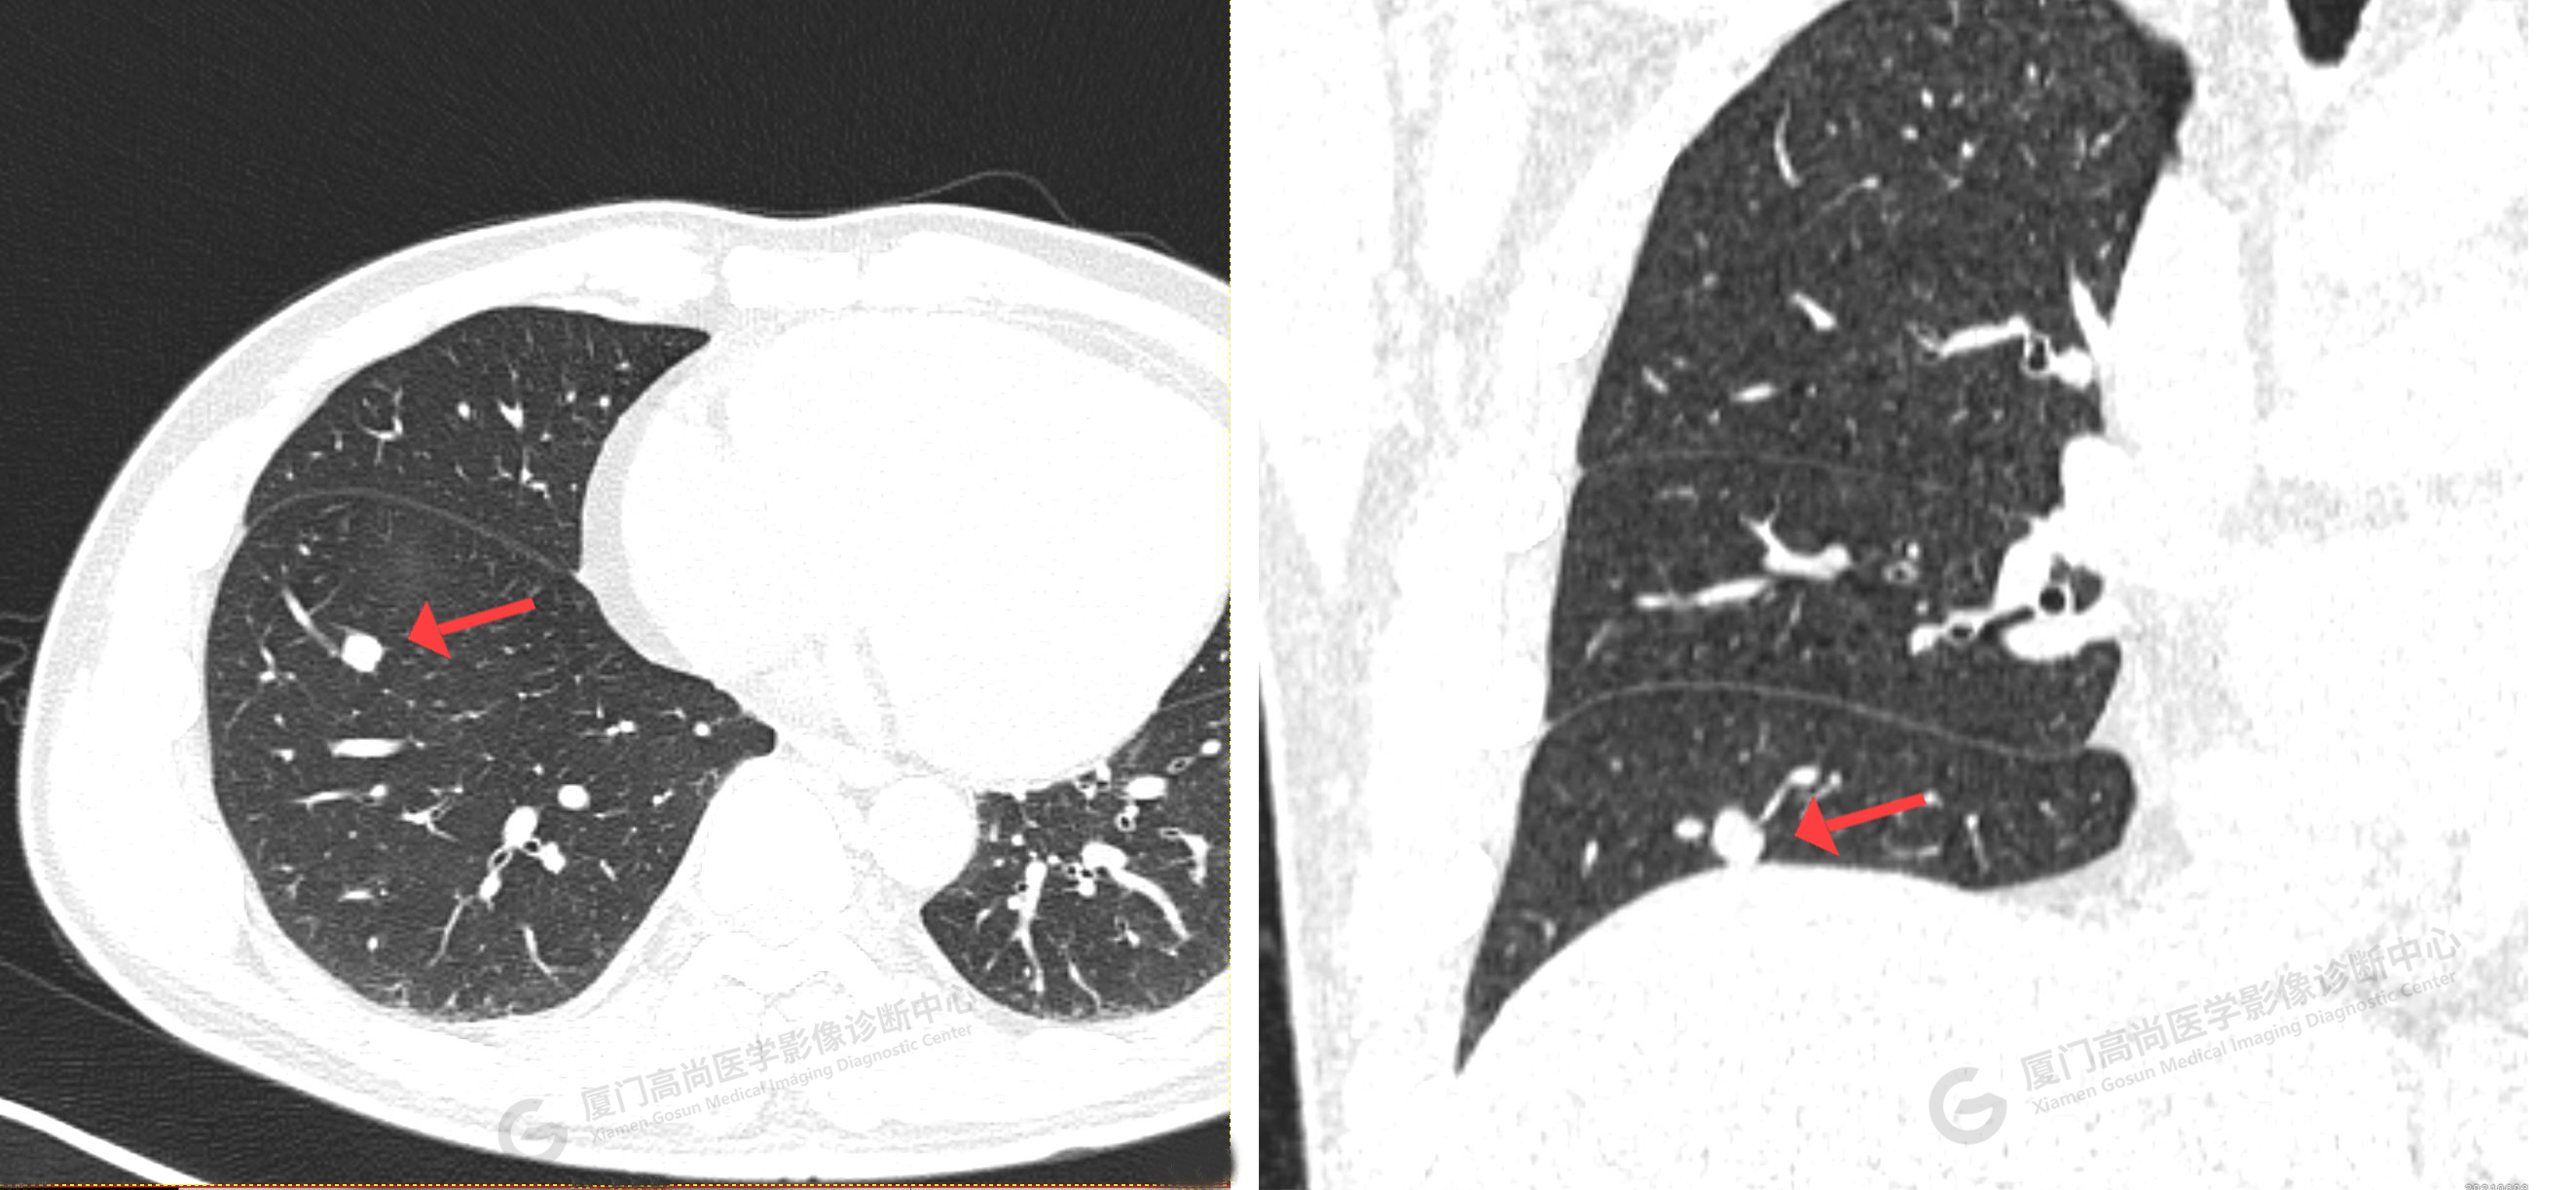

CT影像圖

CT示:右肺上葉尖段磨玻璃結(jié)節(jié),考慮腫瘤性病變可能,建議PET/CT檢查。